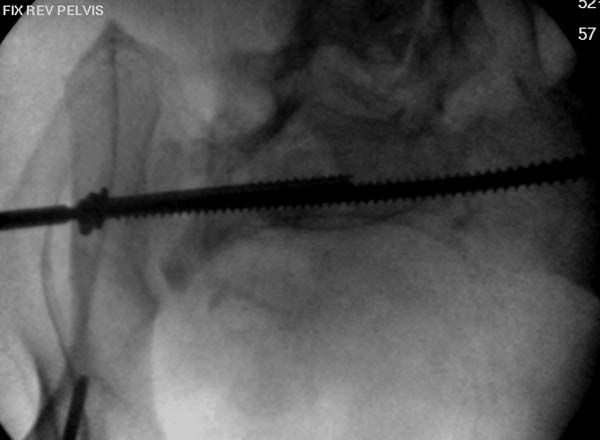

Здесь снимки, которые показывают направление стержня, а также идею

репозиции вытяжением. На рентгенопроницаемых столах имеется возможность

установить дополнительную раму, где по желанию можно увеличить или

уменьшить высоту угла вытяжения. Для репозиции таза больной в положение

на спине, стержень для вытяжения остается во время операции. Система

подойдет для тракции головки бедра из вертлужной впадины, и для этого

стерильная веревка и Synthes Universal Chuck with T-Handle.

Двухстороннее повреждение крестца и травматическая ампутация бедра, где

неопытной бригадой дежурантов установлен верхний наружный фиксатор для

стабилизации. На третий день ревизия на более стабильный, и

окончательная фиксация. Первые снимки после стабилизации таза, и другие,

где показаны (параллельные) правильная установка на AIIS т.е на месте

прикрепления прямой мышцы бедра. Ампутация закончена костно пластическим

методом.